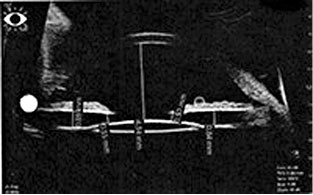

При контрольном осмотре 24.04.2016 жалоб пациентка не предъявляла. По данным ультразвуковой биомикроскопии, зона патологического контакта пигментного листка радужной оболочки с передней поверхностью хрусталика и цинновыми связками стала меньше, но сохранялась (рис. 3, 4). Рекомендовано наблюдение в динамике.

Рис. 3. Правый глаз, ультразвуковая биомикроскопия после лазерной периферической иридотомии

Рис. 4. Левый глаз, ультразвуковая биомикроскопия после лазерной периферической иридотомии